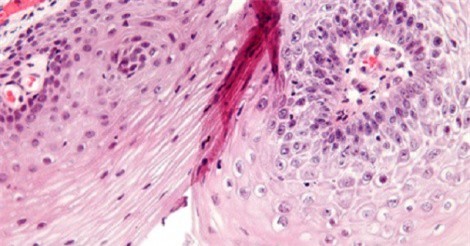

Sùi mào gà là căn bệnh cực kỳ nguy hiểm nhưng rất nhiều người đang hiểu sai về chúng.

Thời gian ủ bệnh 3 tuần đến 8 tháng kể từ khi nhiễm virus HPV mới xuất hiện triệu chứng nốt sùi, chủ yếu ở vùng sinh dục.

(DNVN) - Bệnh sùi mào gà hiện đang là mối lo của các bậc phụ huynh ở Hưng Yên khi con em mình bị bệnh. Một vài triệu chứng sau đây giúp bạn sớm nhận ra bệnh và có cách phòng tránh.